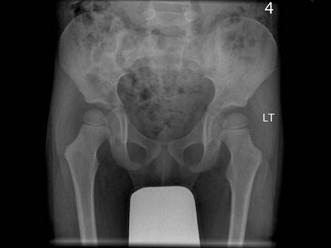

男,请根据其正常骨盆影像图像,判断其最可能的年龄 ( )A、10岁左右B、13岁左右C、4岁左右D、7岁左右E、1岁左右

问题 男,请根据其正常骨盆影像图像,判断其最可能的年龄 ( )

选项 A、10岁左右 B、13岁左右 C、4岁左右 D、7岁左右 E、1岁左右

答案 C